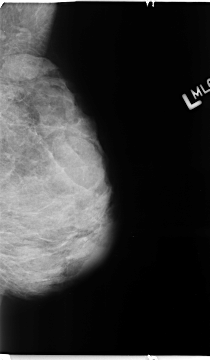

B_3112_1.LEFT_MLO

LEFT_MLO LINES 4680 PIXELS_PER_LINE 2720 BITS_PER_PIXEL 12 RESOLUTION 50 NON_OVERLAY